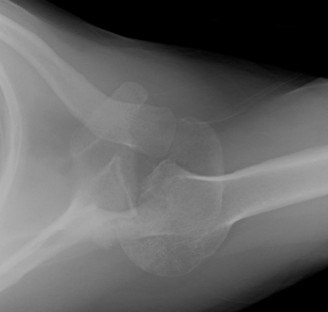

Post-operative radiographs confirmed excellent positioning of the Reverse Total Shoulder Arthroplasty components. The baseplate was flush with the prepared glenoid, the screws were appropriately sized and positioned, and the humeral stem was centrally aligned within the medullary canal with adequate distalization.

Glenoid Reconstruction: The center point for the baseplate was identified. Due to the anterior bone loss, the starting point was shifted slightly posterior and inferior to maximize bone purchase in the native vault. The glenoid was reamed to correct the version and create a concentric surface. Care was taken to avoid over-reaming, which would deplete the already compromised subchondral bone stock. A standard RTSA baseplate with a central compressive screw was impacted into place. Peripheral locking screws were then placed—superiorly into the base of the coracoid and inferiorly down the scapular pillar—achieving excellent rigid, bi-cortical fixation. A standard 38mm glenosphere was then impacted and secured via a Morse taper mechanism.

Humeral Reconstruction: The proximal humerus was prepared using sequential broaches to accommodate the humeral stem. Given the patient's age and bone quality, a cemented humeral stem was selected to ensure immediate rigid fixation and prevent subsidence. A trial reduction was performed using a standard polyethylene insert.